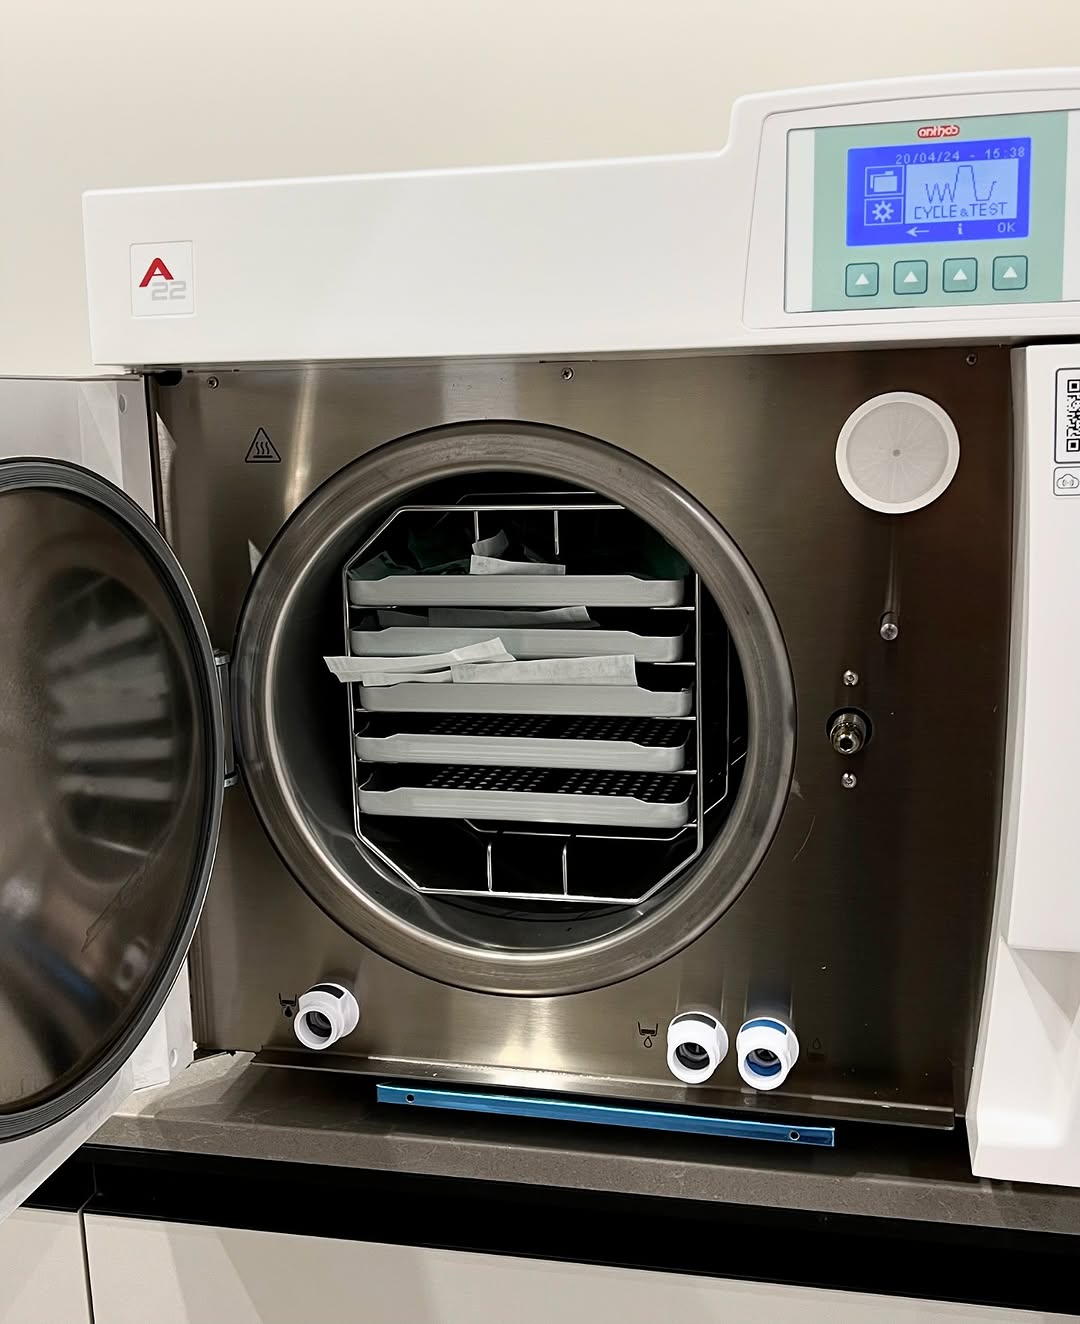

Стерилізація за євростандартами

Ми розуміємо, що безпека — це головний критерій. Тому в Harmony Clinic впроваджено систему «АнтиСНІД» та «АнтиГепатит».